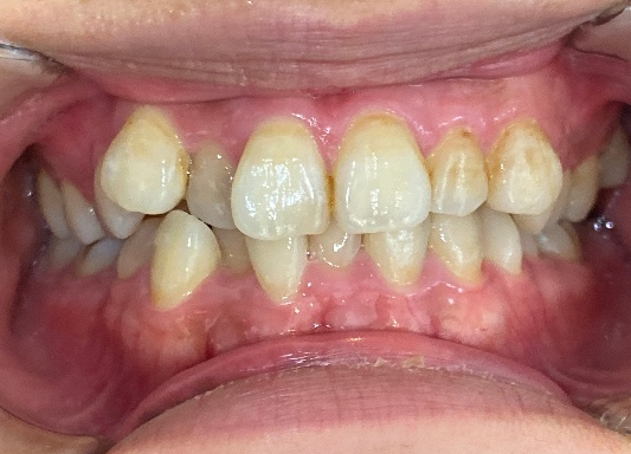

20代女性「オンライン授業中に映る自分の口元が気になる」歯が重なり合ってデコボコしている歯並びをマウスピース型矯正「インビサラインフル」により歯を抜かずきれいに整えた症例

拝見したところ、上下の前歯ともに、歯が重なり合ってデコボコした状態の「叢生(そうせい)」でした。

前歯以外、奥歯にかけて(臼歯部/4番以降)は正常な歯並びでした。

上下前歯が正しい位置に並び、きれいに整いました。